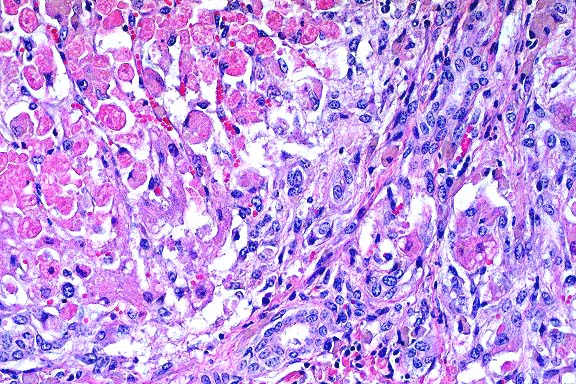

Contributor's Diagnosis and Comments: Liver: Centrilobular

necrosis and hemorrhage, severe, acute, coalescing with centrilobular

hepatocellular disassociation.

Etiology: Toxicosis due to Microcystis aeruginosa ("blue-green

algae") and microcystin-LR toxin.

- Microcystin-LR, a hepatotoxin produced by the blue-green

algae Microcystis aeruginosa, sporadically causes sudden death

in livestock. Typical case histories indicate lagoons or ponds

with a heavy algal bloom that is ingested by drinking livestock.

The ultrastructural lesion, occurring as early as ten minutes

after ingestion, is a rearrangement of the actin cytoskeleton

leading to cell rounding, disassociation, and degeneration. Necrosis

of hepatocytes is observed at 60 minutes. Light microscopic changes

include centrilobular necrosis and hemorrhage, as seen in this

case. Differential diagnosis included bovine pestivirus (bovine

viral diarrhea), Clostridium chauvoei, salmonellosis, lead toxicosis,

and lightning strike.

20x

obj.

- Case 21-4. Liver. There is degeneration, individualization,

and necrosis of hepatocytes throughout the lobule with centrilobular

hemorrhage and hemosiderin deposition.

- AFIP Diagnosis: Liver: Necrosis, massive, with hepatocellular

disassociation and hemorrhage, Hereford, bovine.